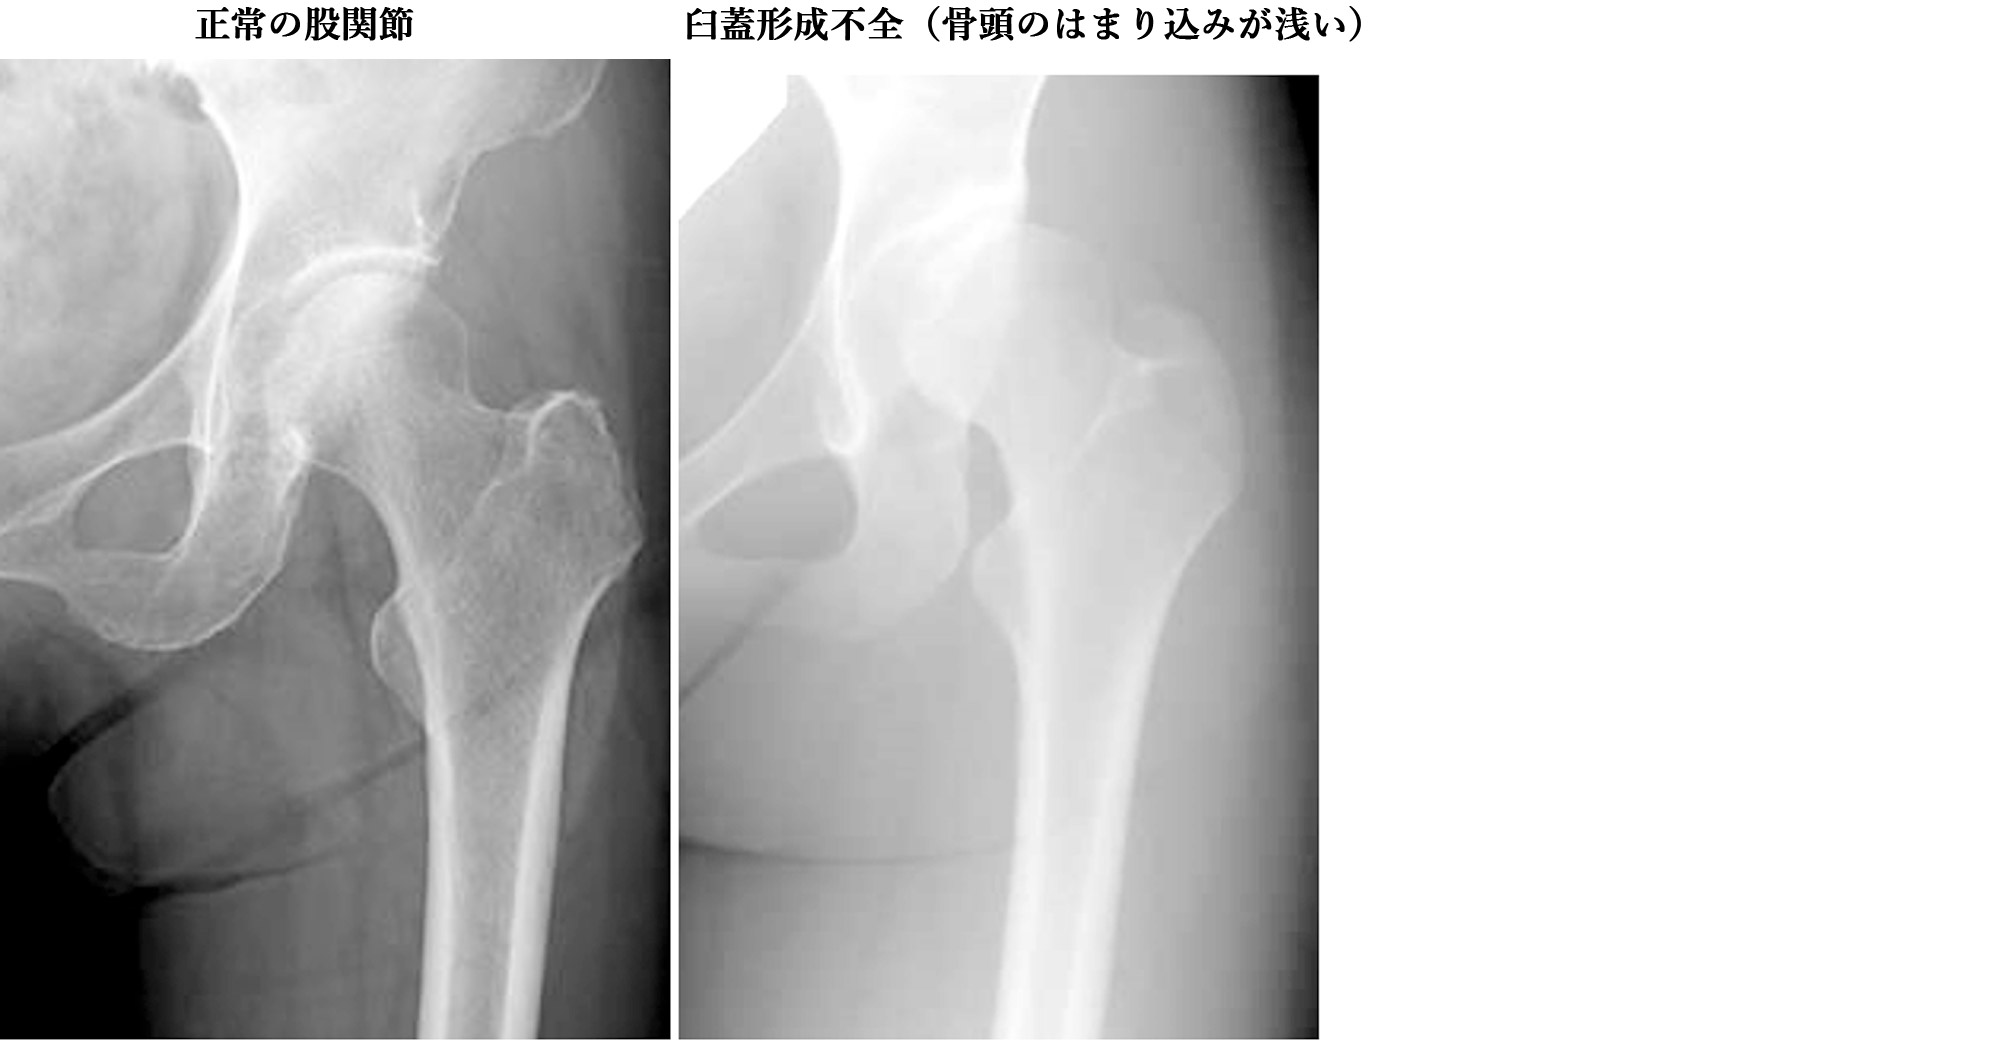

子供の股関節の球関節が脱臼することがあります。これは、ボールが動くとソケットから滑り落ちることを意味します。場合によっては関節が完全に脱臼してしまうこともあります。 American Family Physician によると、乳児 1,000 人に 1 人が股関節脱臼を持って生まれます。

お子様が 18 か月以上である場合、または治療にあまり反応しなかった場合は、股関節を再建するために大腿骨または骨盤の骨切り術が必要になる場合があります。これは、外科医が大腿骨頭 (股関節球) または骨盤の寛骨臼 (股関節窩) を分割または再形成することを意味します。